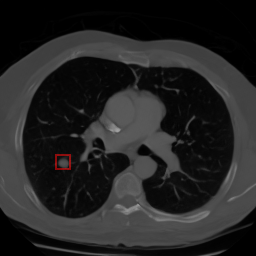

Chest CT synthetic 2D image

Characterization of Synthetic Lung Nodules in Conditional Latent Diffusion of Chest CT Scans

Roger Marí‬, Paula Subías-Beltrán, Carla Pitarch, Mar Galofré, Rafael Redondo

Artificial Intelligence Research and Development, 2024

paper / code / data / doi: 10.3233/FAIA240408

We generate synthetic 2D chest CT imagery using a conditional latent diffusion model guided by bounding-box masks and attribute embeddings. We analyze how well the model controls lung nodule placement and characteristics, highlighting strengths and biases.